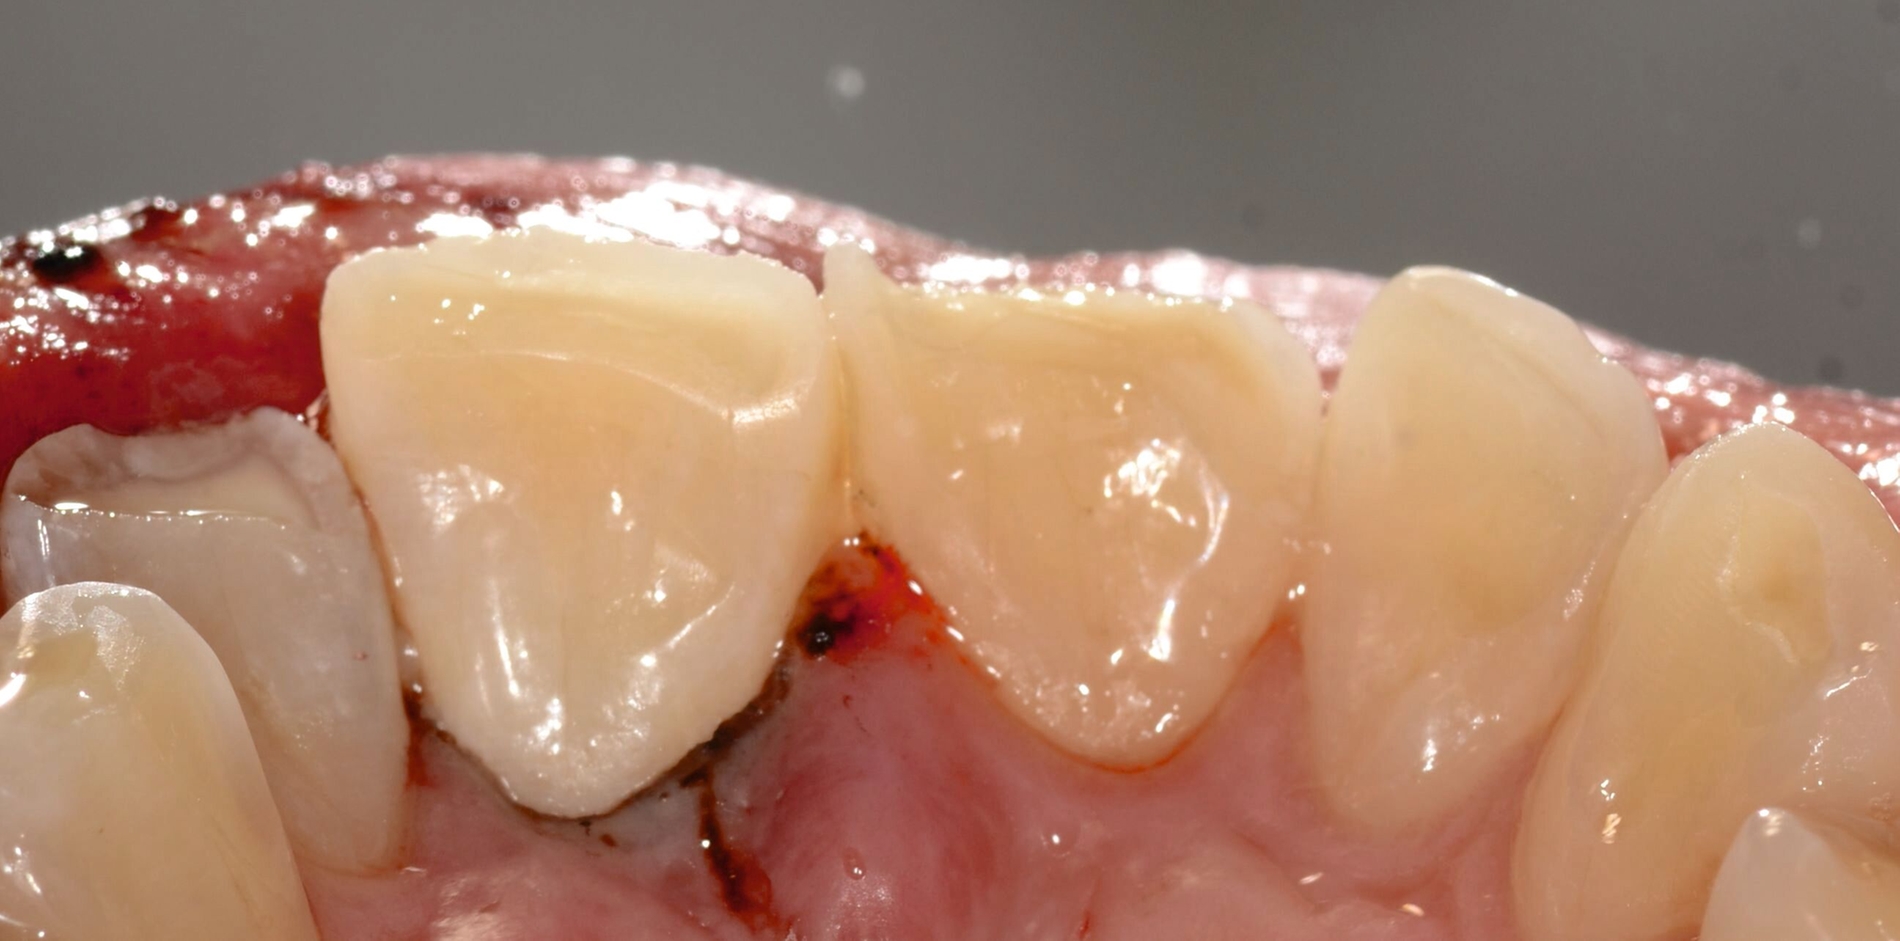

Die adhäsive Konditionierung erfolgt durch ein Ein-Schritt-Adhäsivsystem, das nach dem Auftragen nicht polymerisiert wird, um die exakte Passung des Fragments nicht zu beeinträchtigen. Anschließend wird die Frakturfläche dünn mit einem dualhärtenden Befestigungskomposit bestrichen, anschließend das Fragment repositioniert. Nach vorsichtiger Entfernung der Überschüsse, insbesondere im Sulkus, wird lichtpolymerisiert, abschließend die Okklusion überprüft und der Zahn 11 poliert (Abbildung 2).

Um potenzielle Komplikationen nach einem Zahntrauma möglichst frühzeitig zu erkennen, werden entsprechend den Empfehlungen der S2k-Leitlinie regelmäßige röntgenologische und klinische Nachkontrollen durchgeführt. Exemplarisch sind hier die Röntgenbilder nach drei Monaten und 1,5 Jahren dargestellt (Abbildung 3).